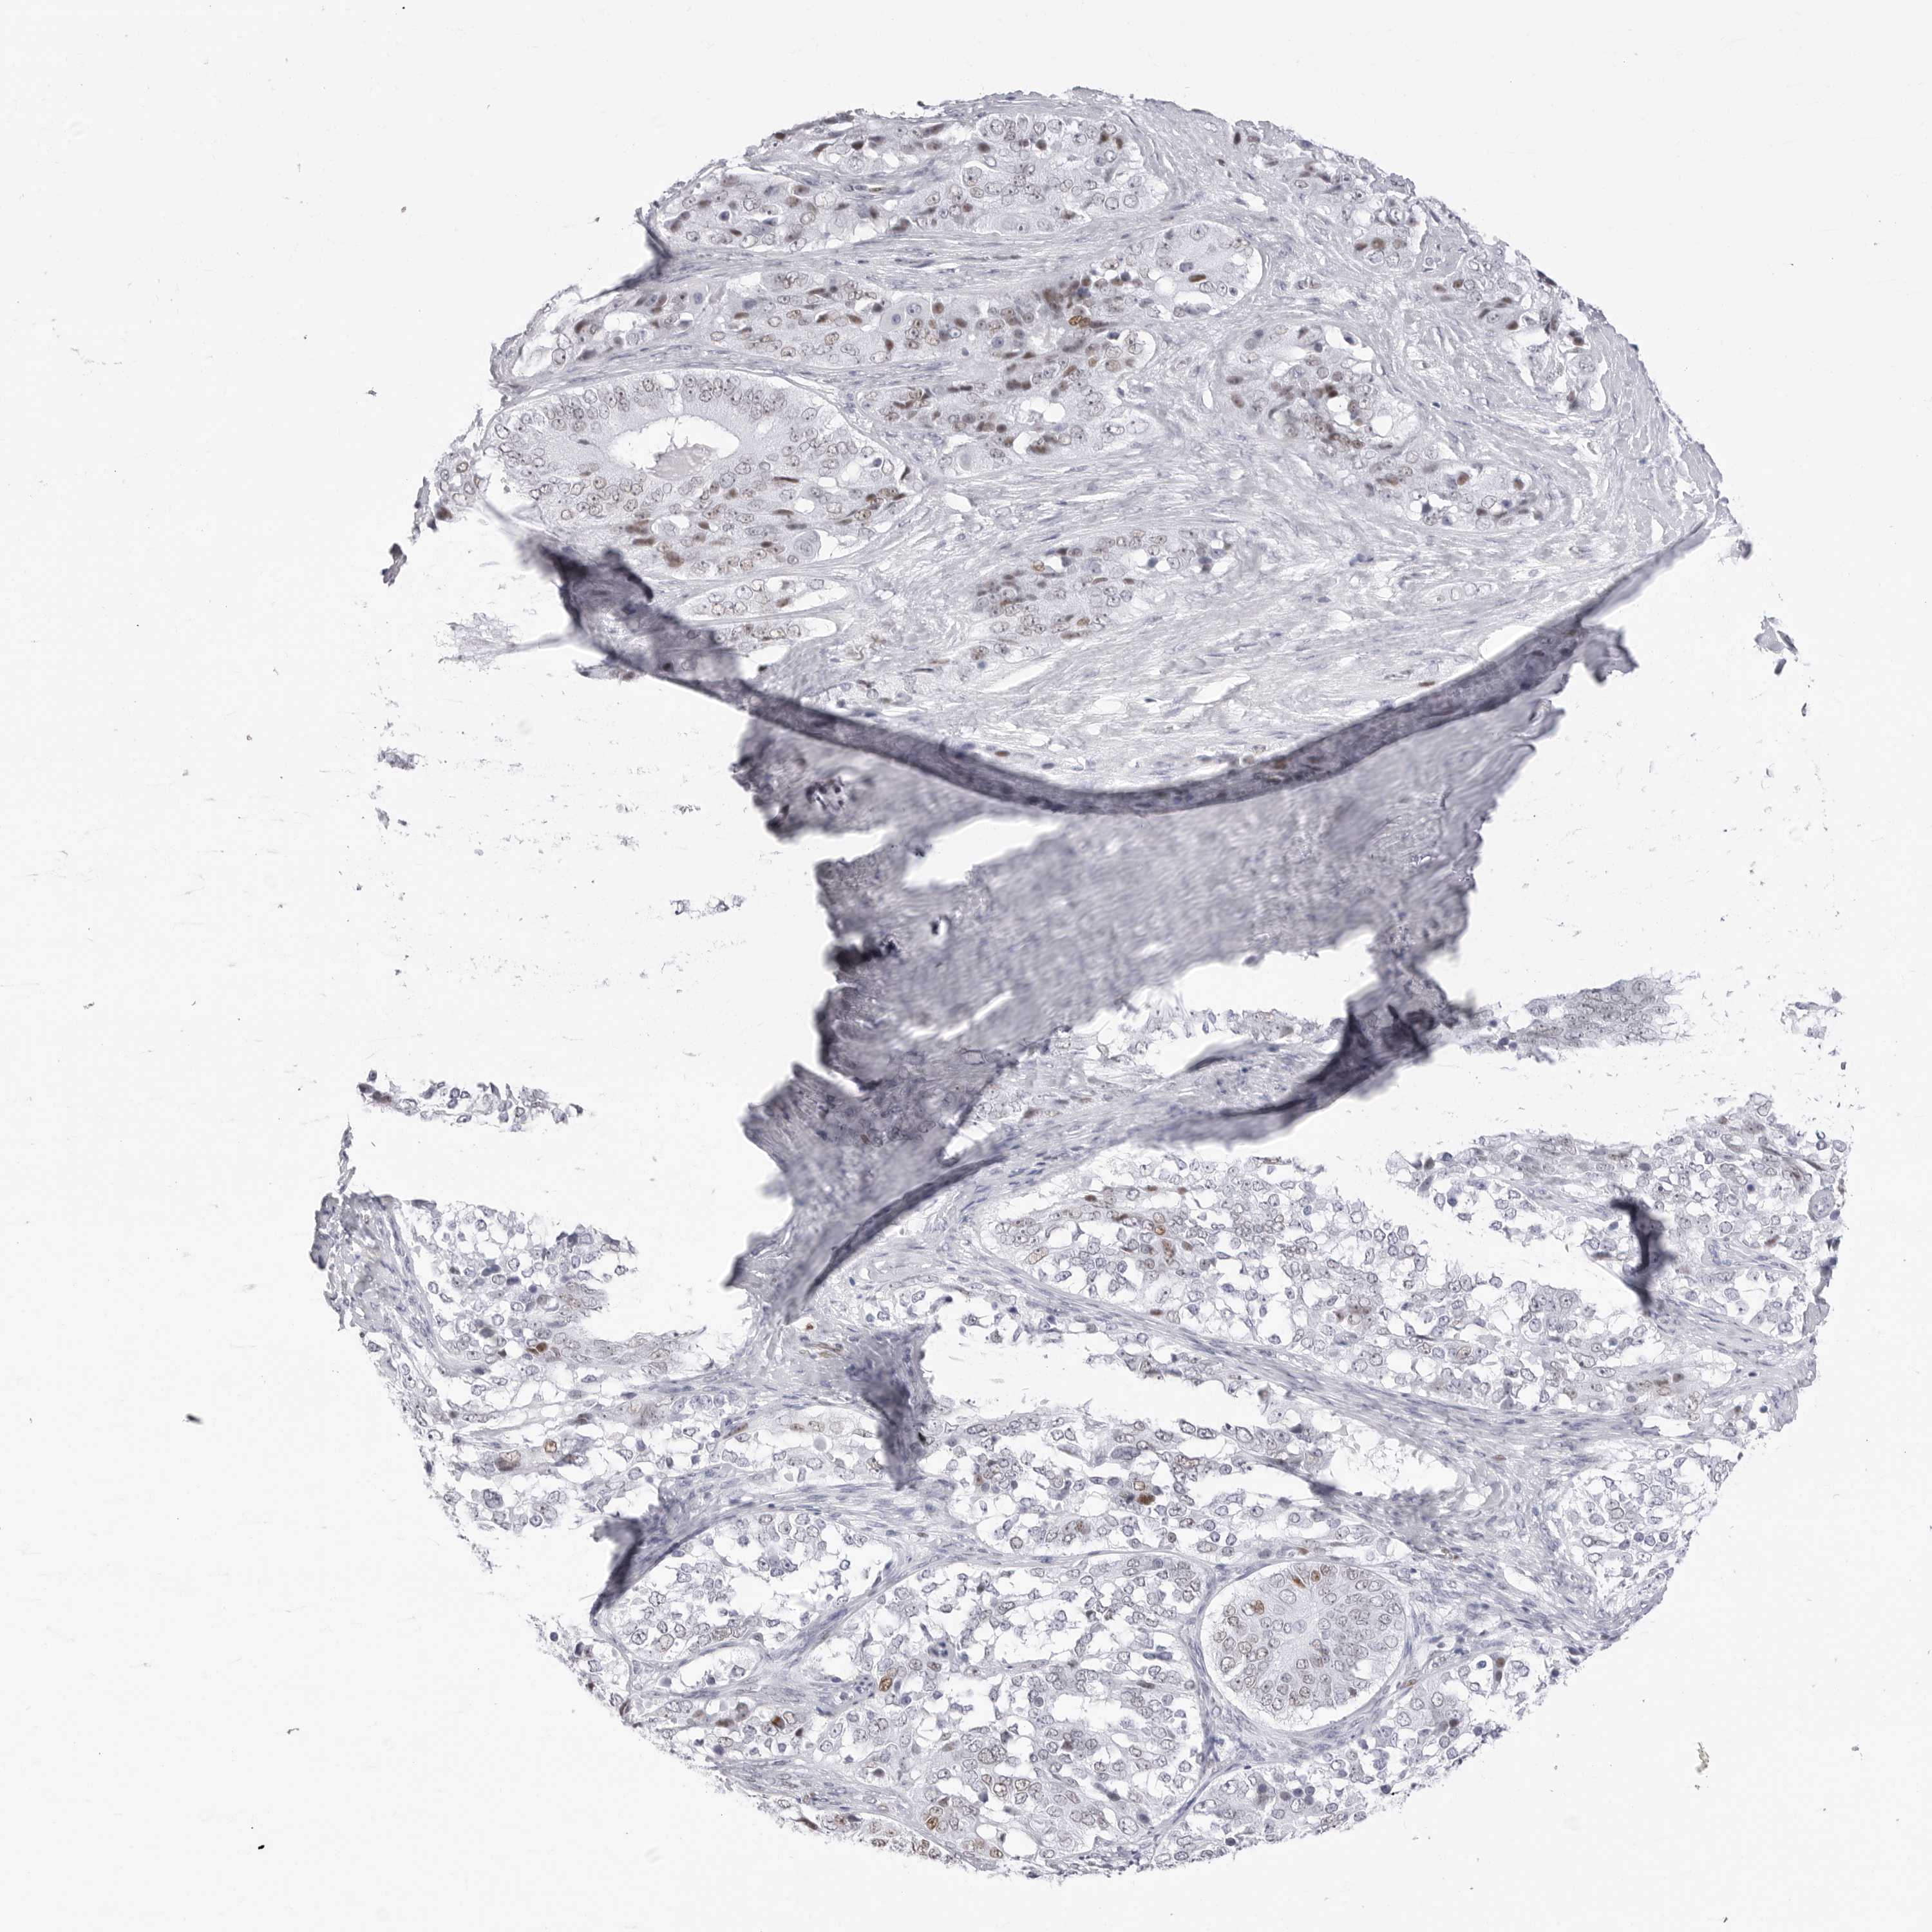

OVARIAN CANCER - Protein expressioni

A mouse-over function shows sample information and annotation data. Click on an image to view it in a full screen mode. Samples can be filtered based on level of antibody staining by selecting one or several of the following categories: high, medium, low and not detected. The assay and annotation is described here.

Note that samples used for immunohistochemistry by the Human Protein Atlas do not correspond to samples in the TCGA dataset.

Antibody stainingi

Antibody staining in the annotated cell types in the current human tissue is reported as not detected, low, medium, or high, based on conventional immunohistochemistry profiling in selected tissues. This score is based on the combination of the staining intensity and fraction of stained cells.

Each image is clickable and will lead to virtual microscopy that enables deeper exploration of all samples and also displays staining intensity scores, fraction scores and subcellular localization as well as patient and tissue information for each sample.

Antibody HPA028136

Antibody HPA030518

Antibody HPA030520

Staining

High

Medium

Low

Not detected

Cystadenocarcinoma, serous, NOS

Carcinoma, endometroid

Cystadenocarcinoma, mucinous, NOS

Carcinoma, NOS